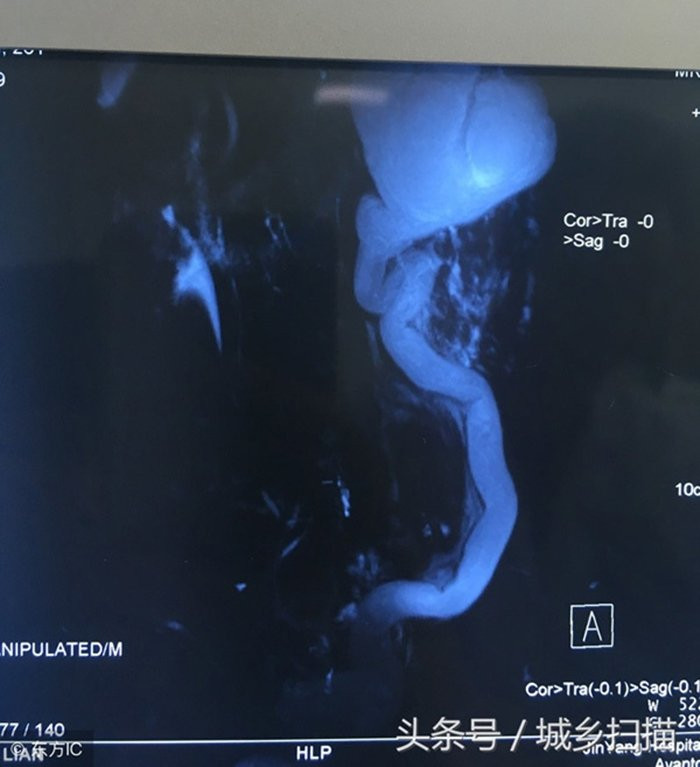

Bác sĩ cho biết, thận trên bên trái của anh bị ứ nước nghiêm trọng, bao phủ và chèn ép thận dưới bên trái, kèm theo nhiễm trùng gây ra một loạt các triệu chứng như đau lưng eo và sốt.

Bác sĩ nói rằng, thận của Vương Khai Luyện xuất hiện ổ bệnh là thận trên bên trái, bên trong có chứa lượng lớn chất lỏng.

Kết quả kiểm tra hình ảnh cho thấy, tràn dịch khiến thận trở nên to gấp 3 đến 5 lần so với ban đầu. Nếu thận trên bên trái không được loại bỏ kịp thời, đồng thời nhiễm trùng sẽ càng nghiêm trọng hơn và cũng có thể gây nguy hiểm cho các thận khác.